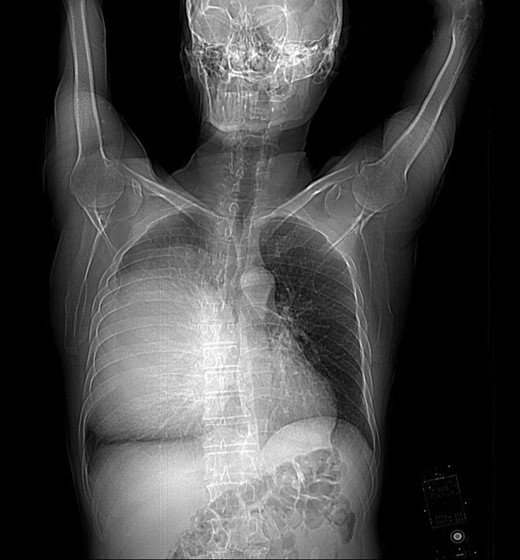

A 68-year-old male presented to our hospital after experiencing exertional dyspnea and shortness of breath for 2 months. He had no other chest complaints, such as cough, hemoptysis or chest pain. His medical history was unremarkable and he had no history of exposure to asbestos. He had no exposure to tobacco. His blood pressure was 136/78 mmHg, pulse was 92 beats/min and respiratory rate was 23 breaths/min. He was afebrile, and oxygen saturation was 94% in room air. Examination of the chest revealed dullness and diminished breath sounds on the right hemithorax. A plain chest X-ray showed a right side huge opacity (Fig. 1). A contrast-enhanced computed tomography (CT) revealed a large heterogeneous mass that almost completely fill the right hemithorax (Fig. 2a and b). CT-guided transthoracic core needle biopsy demonstrated SFTP. Under general anesthesia and with the use of a single lumen endotracheal tube, right posterolateral thoracotomy was performed through fifth intercostals spaces. Upon entering the pleura we visualize a very huge encapsulated mass with adhesion to chest wall (Fig. 3a). After adhesiolysis, the main vascular pedicle of the tumor from the upper lobe was ligated with non-absorbable suture.The well-circumscribed, encapsulated resected mass was measured to be 30 cm × 21 cm × 15 cm and weighed 6900 g in the fresh state (Fig. 3b and c). The postoperative course was uneventful and the patient was discharged on postoperative Day 6. The patient is currently alive without any recurrence twelve months after the surgery. The histological findings revealed spindle tumor cells arranged with varying amounts of collagen and hyalinization of fibrous tissue (Fig. 4a). Mitosis was rarely present. Immunochistochemically tumor cells were reactive for CD34, and bcl2 and typically no immunoreactivity was observed with S-100, WT-1, Desmin, CEA, CK AE1/AE3, CK5/6 and calretinin (Fig. 4b and c). According to the morphology and cellular immunophenotype the diagnosis of benign giant pleural SFT was signed out.

Chest radiography showing a large opacity in the right hemithorax.